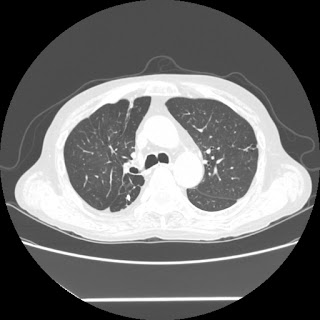

A 58 years old man with....

HRCT done on 17Mar16